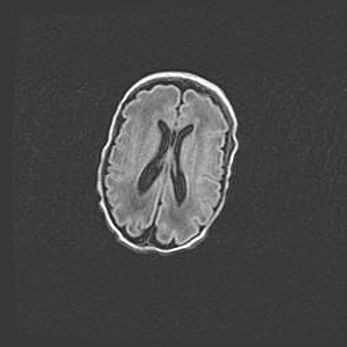

Открытая гидроцефалия.

Возраст: 9 месяцев 12 дней

Вес: 6800 г

Пол: мужской

Окружность головы: 41,5 см

Срок гестации: 28 недель

Гидроцефалия головного мозга у новорожденных имеет характерный признак: опережающий рост окружности головы приводит к визуально хорошо определяемой гидроцефальной форме сильно увеличенного в объёме черепа. Детские неврологи определяют следующие симптомы гидроцефалии у грудничков: выбухающий напряжённый родничок, частое запрокидывание головы, смещение глазных яблок к низу.